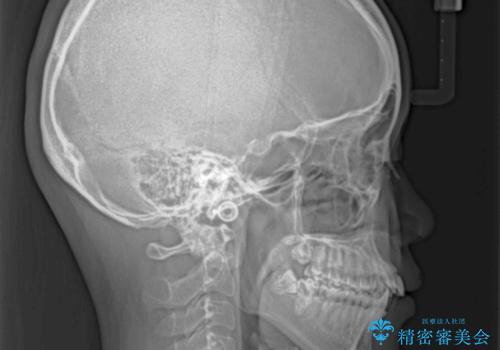

- 前歯の突出感を気にして来院された患者様です。

奥歯の咬み合わせは理想的な咬合に近く、インビザラインでも十分に対応できる歯列でした。

舌の突出癖を改善するためのトレーニングを行いつつ、上下歯列全体を後方に移動させ、更にはIPR(歯と歯の間を削る)によりスペースを獲得することで、口元の突出感を改善することとしました。